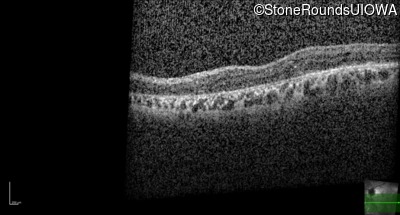

Optical Coherence Tomography - Right - 20/25 -2

Exemplar / OCT Stack

OCT Stack

Optical Coherence Tomography - Left - 20/200